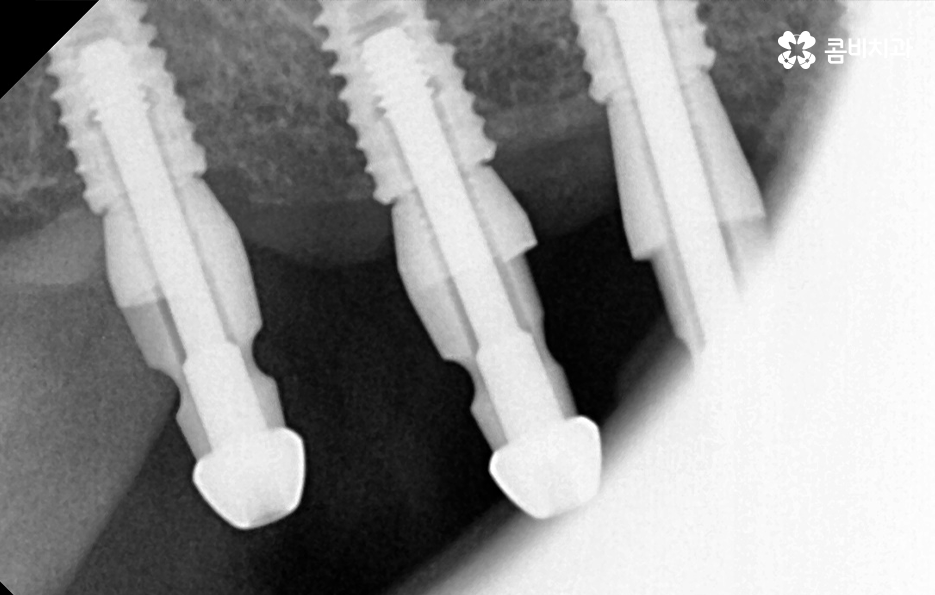

우리가 보편적으로 생각하게 되는 임플란트 치료기간의 경우 치아 하나를 상실하고 임플란트를 1:1로 치료할 때 예상 기간에 대해서 고려하게 되는 경우가 기본적인 접근 방법이라면 실질적으로 치과에서 임플란트를 하게 되는 연령대를 보더라도 보통 50대에서 60대 이후에 치아를 상실하게 되는 환자분들이 급증하기 때문에 위 사진의 사례처럼 여러 치아를 상실하고 임플란트를 식립하게 되는 경우도 많을 거예요